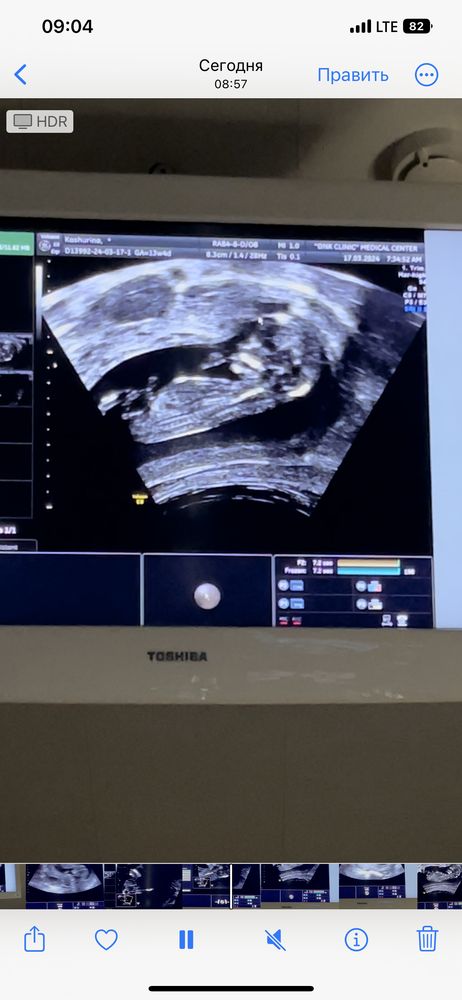

Девочка или мальчик ? 12 недель 5 дней

Анализы, скринингиПомогите 🤣 первый скрининг был сегодня )

врач молчаливая .. сначала сказала вроде девочка потом сказала на мальчика похоже и все 🤷🏼♀️

По первому фото девочка. На втором непонятно что это, на бугорок не очень похоже

Оооо:) на первом фото реально девочка, на втором 100% мальчик😁 как будто фотки двух разных пупсиков